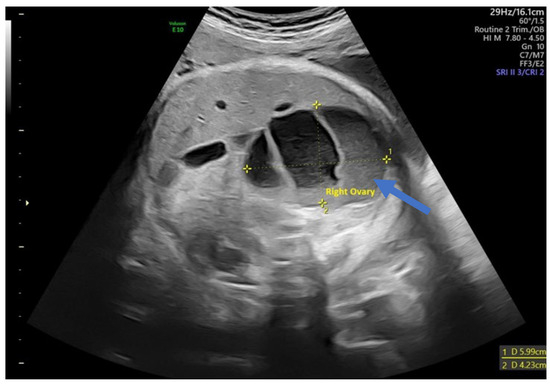

In 75% of the cases diagnosed, the cyst had the appearance of a simple cyst. Ultrasound revealed a unilocular, echoless cyst that was well circumscribed, had thin walls, and in some cases had multiple intracystic septa. The “daughter cyst sign” was present in four cases (33%) in the form of a small, round, anechoic structure within the cyst (Figure 3).

Figure 3.

Ultrasound axial view. Simple ovarian cysts in the 33rd week of pregnancy. Smaller cysts (arrows) are daughter cysts that are present on both sides.